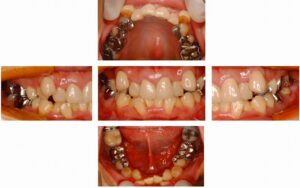

昨日ブログの患者様の治療前の状態を見てみたいというご希望もありました。 下の写真をご覧頂くと、かなり前歯が重なってる叢生(そうせい)という状態でした。 一般的には、八重歯とか言います。このようにかなり叢生が強い時には、やむなく 抜歯をして隙 […] 本文を読む